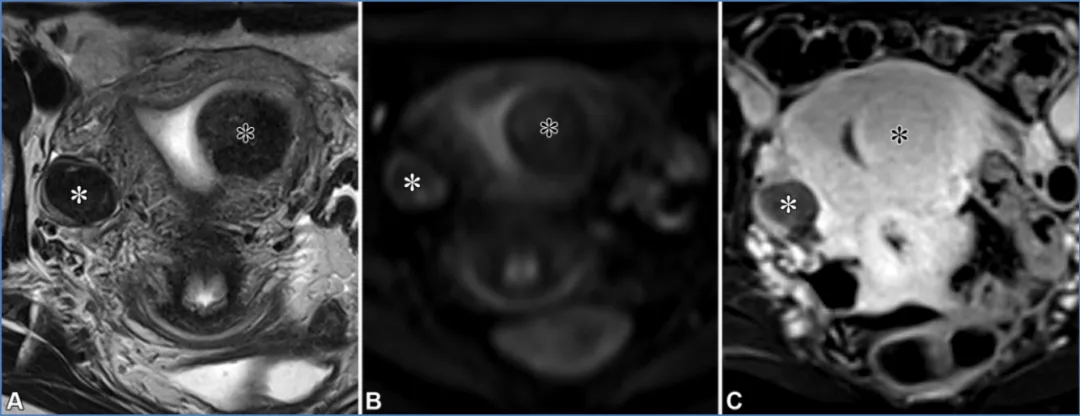

附件区病变——对于卵巢来源的病变,实性病变中具有T2低信号/DWI低信号实性组织的主要考虑为纤维瘤和卵泡膜纤维瘤,而囊性病变中具有T2低信号/DWI低信号实性组织的则考虑为囊腺纤维瘤(36)。卵巢纤维瘤和卵泡膜纤维瘤是良性的、常无症状的性索间质肿瘤,通常发生于中年女性。它们含有纤维组织和卵泡膜细胞。虽然通常为单侧,但双侧纤维瘤可能发生在戈林(基底细胞痣)综合征中。梅格斯综合征(胸腔积液、腹水和卵巢肿块)较为罕见,但在卵巢纤维瘤中比在其他卵巢肿瘤中更常见。卵巢纤维瘤和卵泡膜纤维瘤通常表现为T2低信号/DWI低信号实性组织,伴有T2黑out模式和轻微的延迟强化(图24)。布伦纳瘤是罕见的上皮-间质肿瘤,难以与纤维瘤和卵泡膜纤维瘤鉴别,但通常体积较小(36)。囊腺纤维瘤是一种良性上皮肿瘤,是具有T2低信号/DWI低信号实性组织的囊性病变的最可能诊断(图25)。偶尔,实性组织中可包含散在的囊性病灶,称为“黑色海绵”(36,72)。“黑色海绵”征是一种非特异性特征,也可能在其他较不常见的病变中出现。

图24. 一名37岁痛经女性患者的右侧卵巢纤维瘤和左侧壁内平滑肌瘤(带有黏膜下成分)。(A、B)轴位T2加权像(A)和高b值扩散加权像(B)显示右侧卵巢纤维瘤呈T2低信号/扩散加权低信号(白色*),左侧子宫平滑肌瘤(黑色*)。(C)轴位对比增强脂肪抑制T1加权减影像显示,与平滑肌瘤(黑色*)的明显强化相比,纤维瘤(白色*)仅有轻度强化。

图25. 一位72岁女性患者的囊腺纤维瘤,该患者有腹痛症状且可触及盆腔肿块。(A、B)轴位T2加权像(A)和高b值扩散加权像(B)显示右侧卵巢多房性病变,包含囊性成分和实性组织(箭头),该实性组织在T2加权像和扩散加权像上均呈低信号。注意散在分布于实性组织之间的囊性病灶,即“黑色海绵”(A中的箭头头),这是一种非特异性表现,也可见于其他不太常见的卵巢肿瘤。(C)轴位对比增强脂肪抑制T1加权减影像显示实性组织内有轻度强化(箭头)。